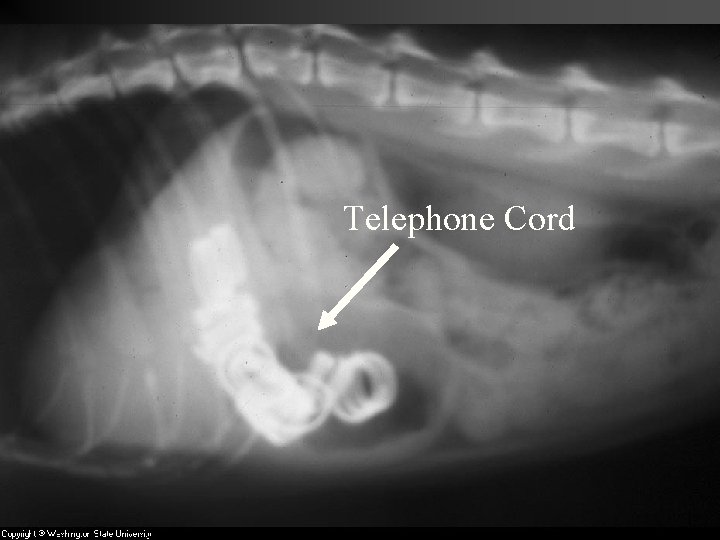

A. Reticulum Tough, honeycomb like structure, puncture resistant, lower portion of the n ‘Catches’ foreign objects and prevents them from causing further harm downstream of the rumen. n Once items “sink” and are “caught” they stay there forever unless removed n

Telephone Cord

Wire